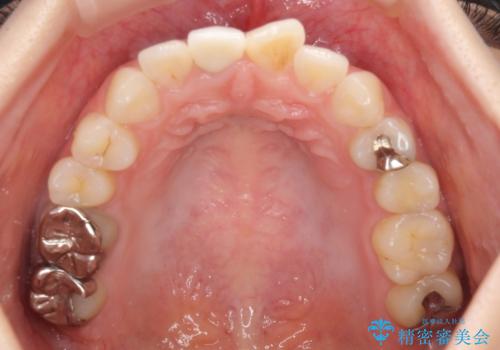

歯は神経をとると、だんだん黒くなることがあります。今回はセラミックで歯を覆うことにより、見た目の改善を図りました。

患者様のご希望で、最終的な色を決める前に、ホワイトニングをしました(約3万円)。ただし、ホワイトニング直後は色が白くなりすぎる等の恐れがあるため、色が落ち着くのを待ってからセラミックを製作しました。